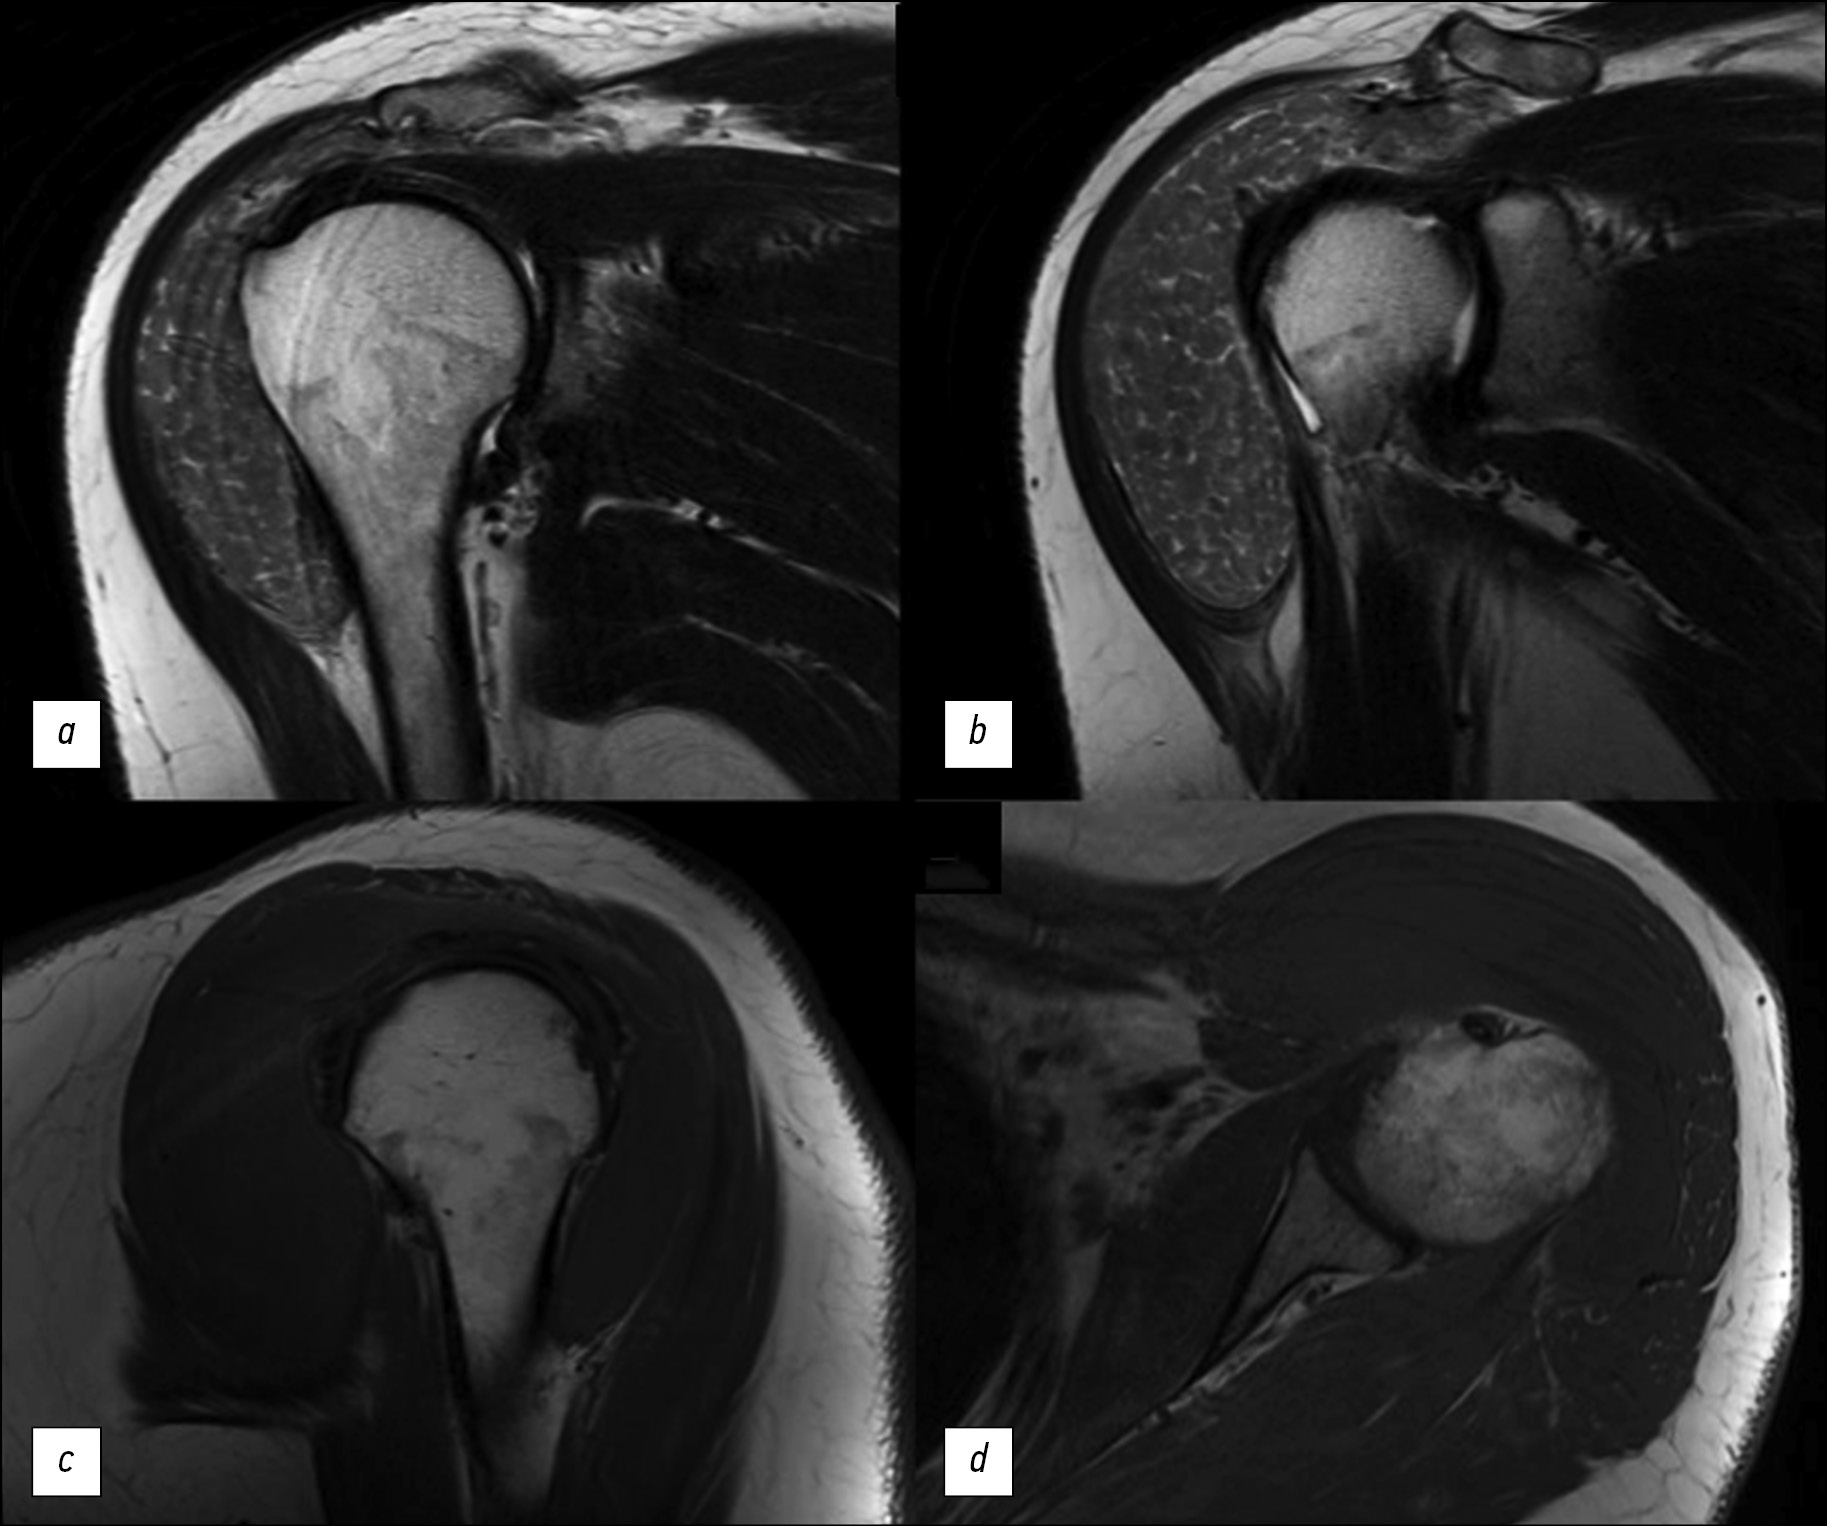

Tissue sampling and histopathological limitations in esophageal cancer

Esophageal adenocarcinoma is a common gastrointestinal cancer. Esophagogastroduodenoscopy with biopsy and immunohistochemistry are used to detect the neoplasm at an early stage. Definitive diagnosis requires not only highly specialized equipment but also the skills of the endoscopist and pathologist. We report the case of a 35-year-old man with progressive dysphagia caused by gastroesophageal cancer. Numerous esophagogastroduodenoscopy studies, computed tomography, and barium X-ray swallow revealed an extensive esophageal lesion; however, pathomorphologic examinations did not confirm malignancy within a year. Histological studies showed pyloric gland adenoma and adenoma from parietal or oncocytic cells with high-grade dysplasia. Esophagogastroduodenoscopy with targeted biopsy at a specialized center confirmed the tumor malignancy. This clinical case demonstrates the importance of summing clinical symptoms and using additional instrumental methods to make a definitive diagnosis if biopsy results are ambiguous.

633-642